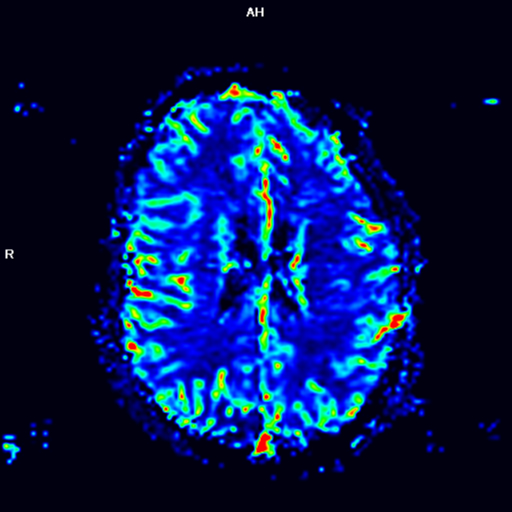

Prueba diagnóstica no invasiva que consiste en la obtención de imágenes de alta definición anatómica de las órbitas mediante el empleo de un campo electromagnético y ondas de radio (con un emisor y un receptor). No utiliza radiación ionizante. Indicaciones: visión doble, traumatismo, sospecha de tumor, hipertiroidismo.